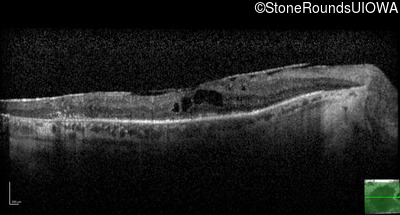

AR Retinitis Pigmentosa (IA1aiii)

Age at visit: 46 years

This 46 year old man has had poor vision in dim light since age 2.

Diagnosis & molecular findings

AR Retinitis Pigmentosa SLC24A1 Met252 del2ggaAT Leu1052 del2ctTC AR